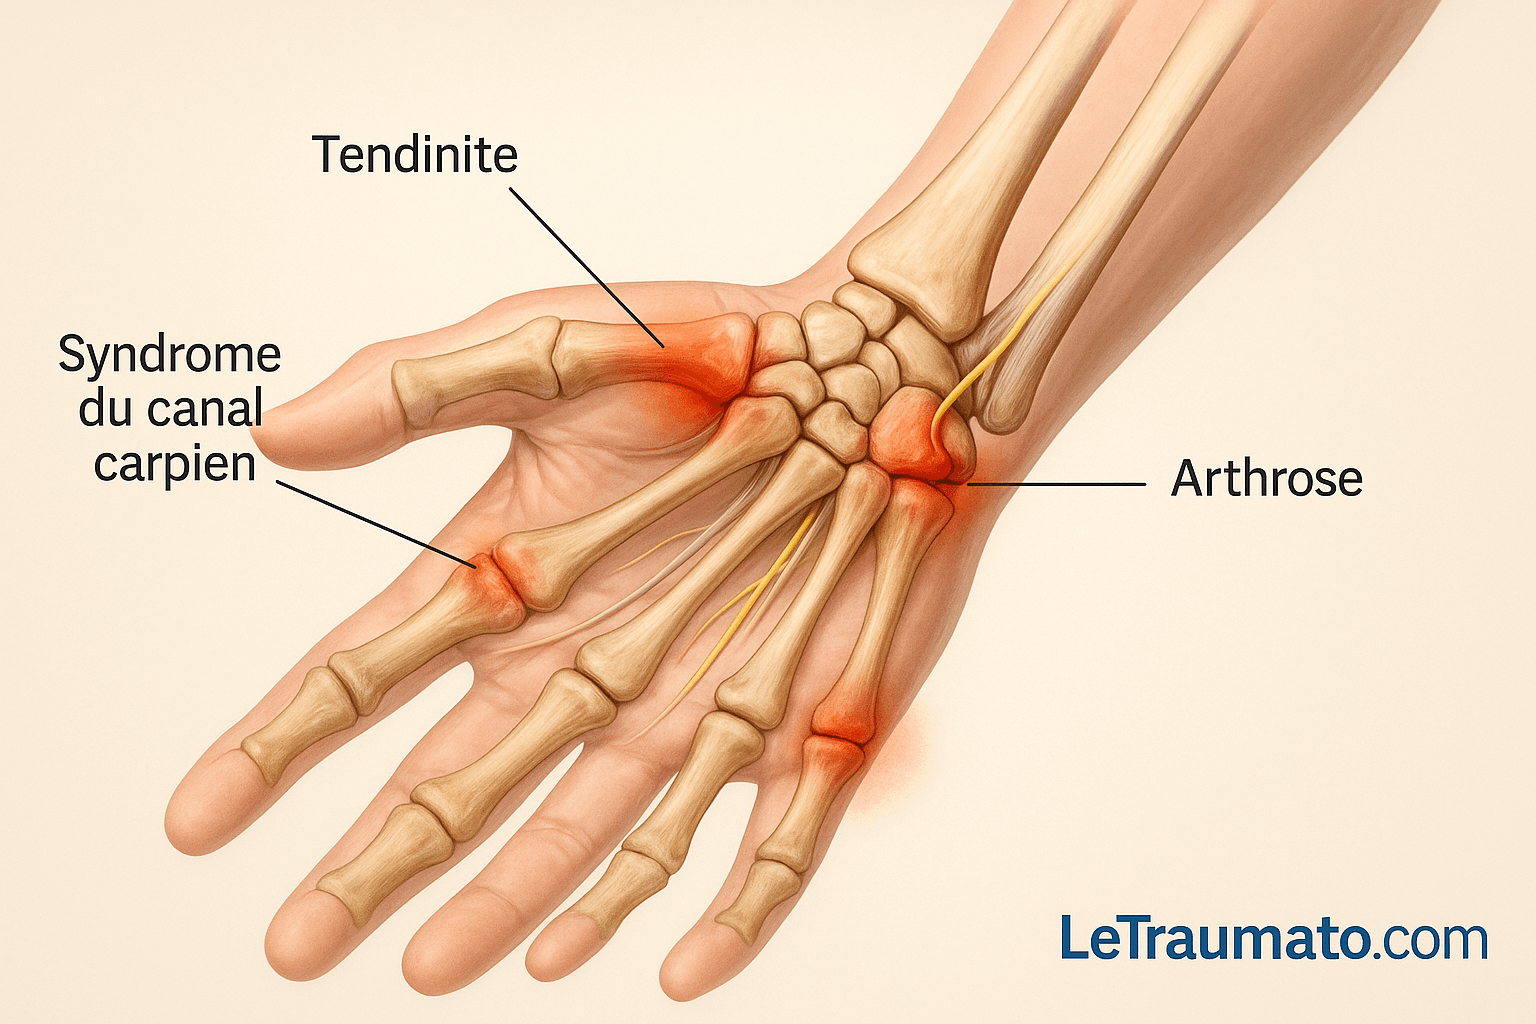

Causes les plus fréquentes de la douleur au poignet

Tendinite du poignet : surmenage et gestes répétitifs

La tendinite du poignet est l’une des causes les plus courantes. Elle survient lorsque les tendons qui relient les muscles aux os sont enflammés. Cette inflammation est souvent due à :

Syndrome du canal carpien

Ce syndrome est causé par une compression du nerf médian dans le canal carpien. Il entraîne :

Arthrose du poignet

L’arthrose résulte de l’usure du cartilage. Elle est souvent secondaire à un traumatisme ancien ou à une maladie inflammatoire. Elle provoque :

- douleur mécanique,

- raideur articulaire,

- craquements.